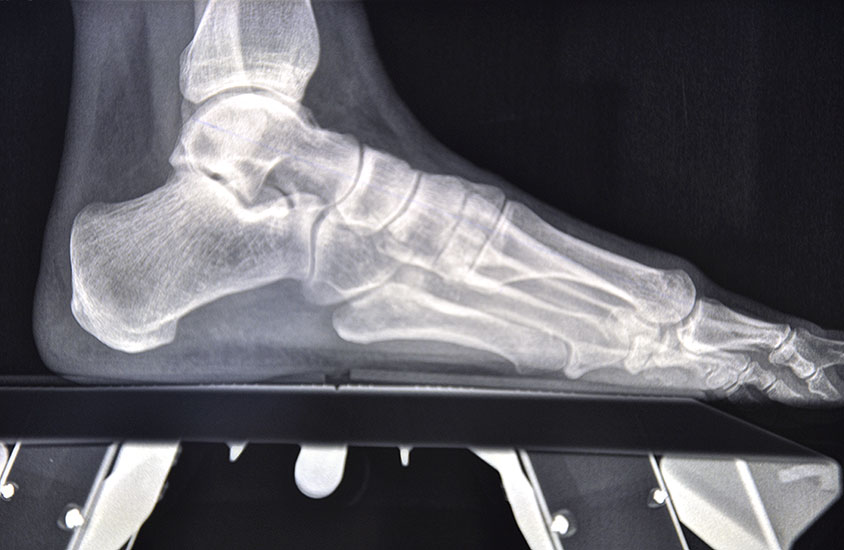

Die primäre Therapie von belastungsabhängigen Beschwerden im Vorfußbereich ist konservativ. Im Rahmen der Diagnostik werden Röntgenbilder des ganzen Fußes im Stehen angefertigt, um die statischen und funktionellen Verhältnisse des Vor- und Rückfußes zu beurteilen.

• Klinische Untersuchung, Anamnese, Bildgebung mit Röntgen des Fußes unter Belastung in mindestens 2 Ebenen.

Die Fäden werden nach der 2. postoperativen Woche gezogen. Der Verbandsschuh wird für 4-6 Wochen getragen, anschließend erfolgt eine Röntgenkontrolle (Abb.16). Das Führen eines Kraftfahrzeuges mit diesem Schuh ist nicht gestattet. Eine Ausnahmekombination stellt die Operation des linken Fußes und Automatik-Fahrzeug dar.